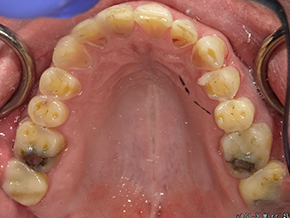

This patient is very happy with his great SureSmile® results, and we are just as happy!